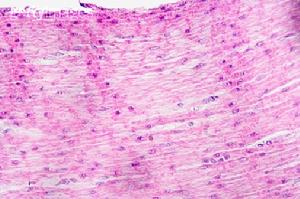

(2)枯萎期:放療幾周后壞死組織脫落,管壁變薄,黏膜變得平滑。一些患者仍可出現明顯的食管平滑肌異常。此期易發生食管出血、穿孔。

(3)再生期:放療數月後基底層殘存的細胞開始再生,逐漸向上延伸、移行,表層重新覆蓋新生的上皮細胞。此期,由於放射引起的血管和組織損害,逐漸出現纖維化。食管變細、狹窄,並且食管運動障礙加重。